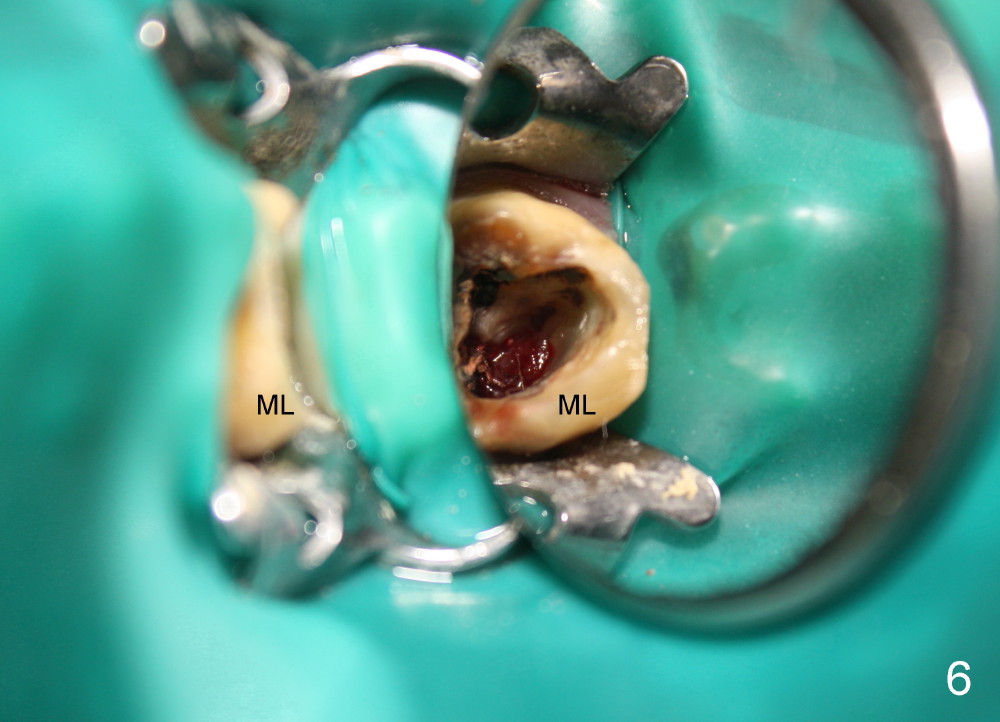

A 49-year-old man has multiple restoration (Fig.1). The tooth #14 appears to be non salvageable (Fig.2-6). The most interesting observation is that the sinus floor (Fig.1 ^) appears to be coronal to the tips of all three roots (mesiobuccal (MB), distobuccal (DB) and palatal (P)). This anatomic feature is confirmed by CBCT study (Fig.2). It will increase insertion torque of an implant to be placed if the sinus floor is raised among the root tips. That is, the apical portion of a large implant is engaged to the area among the apical portion of the three sockets. Let us use Fig.2 Coronal section for design of immediate implant with sinus lift. Click each figure for narrative.